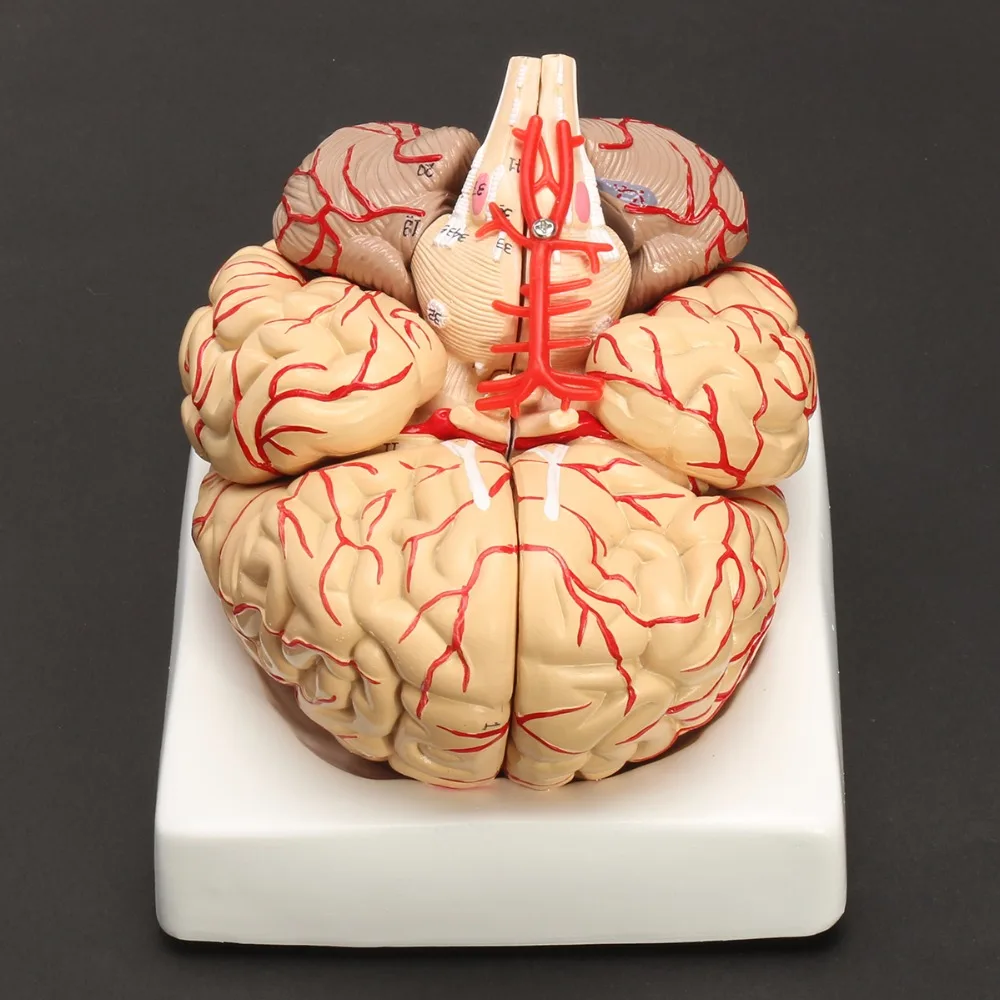

Головной мозг и артерии основания мозга (3D-модель)